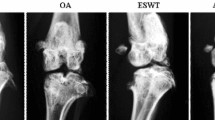

Gross morphology

Cartilage from control group had a normal appearance. Minimal fibrillation was the greatest gross change at 4 weeks, but at 8 weeks, some knees showed fibrillation and erosion (Moran grades 3 and 4) (Fig. 2a). Cartilage lesions were less severe in OA + ESWT than OA-alone rabbits (Moran grade 3 vs. 4), with no significant differences between the 2 groups at 4 weeks (P > 0.05) but significant differences at 8 weeks (P < 0.01). Gross morphology revealed a significant therapeutic effect of ESWT at the later period.

Macroscopy and histomorphologic evaluation at 4 and 8 weeks. a Macroscopy grading of lesion changes to the femoral condyles and tibial plateaus in rabbits. b Cartilage sections were evaluated by a Mankin scoring system. Data are mean ± SD. ## P < 0.01, compared with control group. **P < 0.01, between ACLT + ESWT and ACLT group